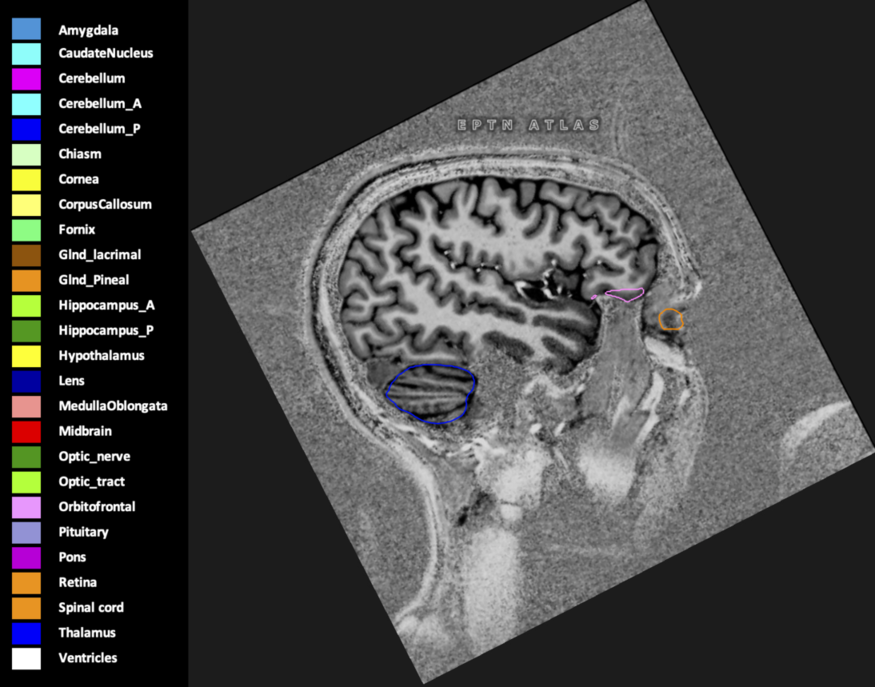

Eekers et al. have published an international neurological atlas for contouring of organs at risk in consensus with the European Particle Therapy Network (EPTN) in 2018 and an update in 2021. The purpose of this consensus atlas is to decrease inter- and intra-observer variability in delineating OARs relevant for neuro-oncology.

Included are all OARs known to be relevant for radiation-induced toxicity in neuro-oncology: brain, brainstem (midbrain, pons, medulla oblongata), chiasm, cerebellum (anterior & posterior), cochlea, cornea, hippocampus (anterior & posterior), hypothalamus, lens, lacrimal gland, optic nerve, pituitary, skin, and vestibular & semicircular canals. To further facilitate research on cognition, vision and radiological changes after irradiation of the brain, potential clinically-relevant OARs are included: amygdala, caudate nucleus, cerebellum (anterior & posterior), corpus callosum, fornix, macula, optic tract, orbitofrontal cortex, periventricular space (PVS), pineal gland, and thalamus.

Three-dimensional delineation of the 25 consensus OARs for neuro-oncology are shown on CT (WW/WL 120/40, 3000/600), 3T MR images, (T1Gd, T2FLAIR 1mm) and 7T MR (MP2RAGE 0.7 mm). All are presented in transversal, sagittal and coronal view.